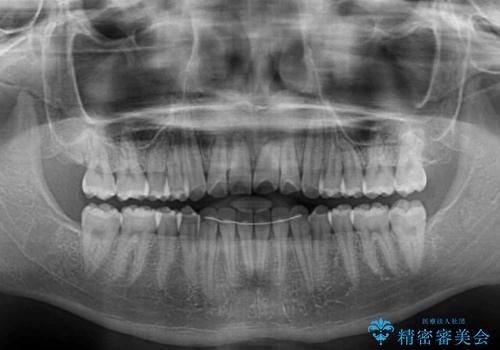

美容歯科でも断られた 著しい前歯のクロスバイトをワイヤー矯正で改善

- 前歯のクロスバイトを気にして来院された患者様です。

美容専門の歯科医院を受診したところ、セラミックでの改善は無理と断られてしまったとのことでした。

歯がすり減って不揃いの形態となっていますが、まずは矯正治療によりクロスバイトを改善することとしました。

治療期間を極力短くしたいとのことで、ワイヤー矯正により治療を行うこととしました。

今後はすり減ってしまった歯の形をセラミッククラウンで改善したいとのことで、クロスバイトが改善し咬みやすくなった時点で装置を外すこととしました。

1年で治療を終えることができ、患者様には大変満足していただきました。